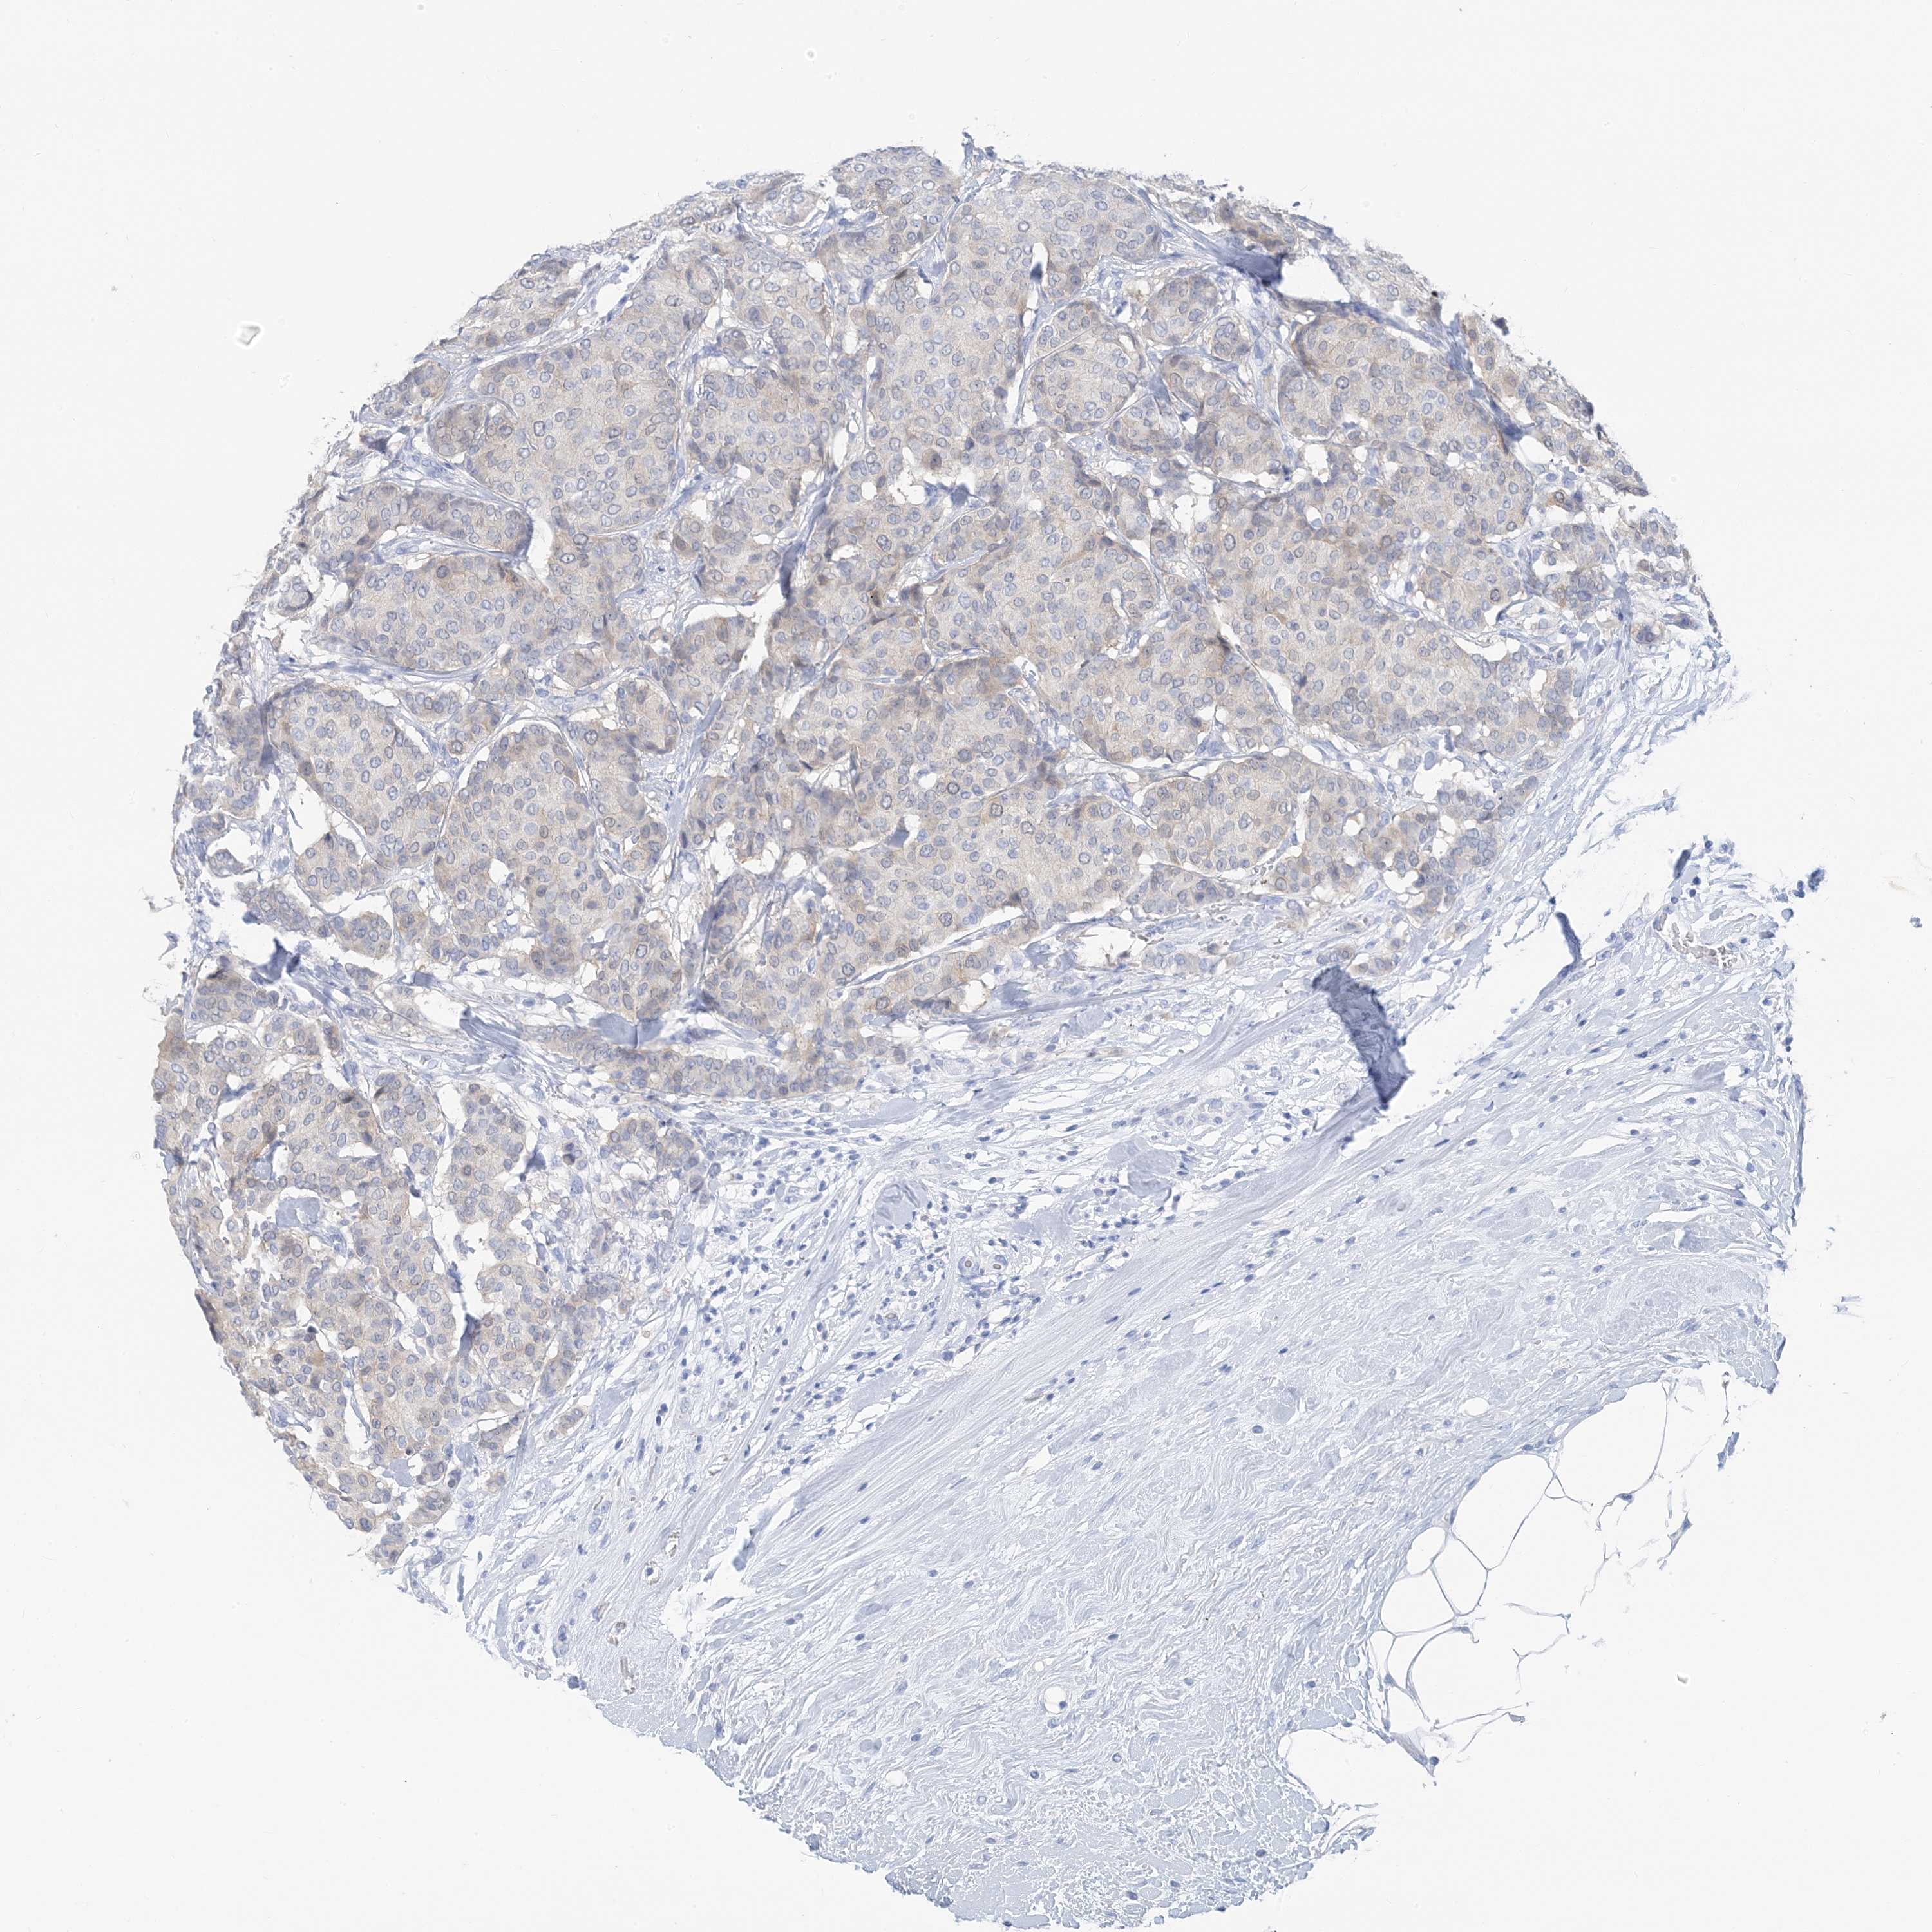

CANCER BREAST CANCER Show tissue menu

Breast cancer

Human cancer